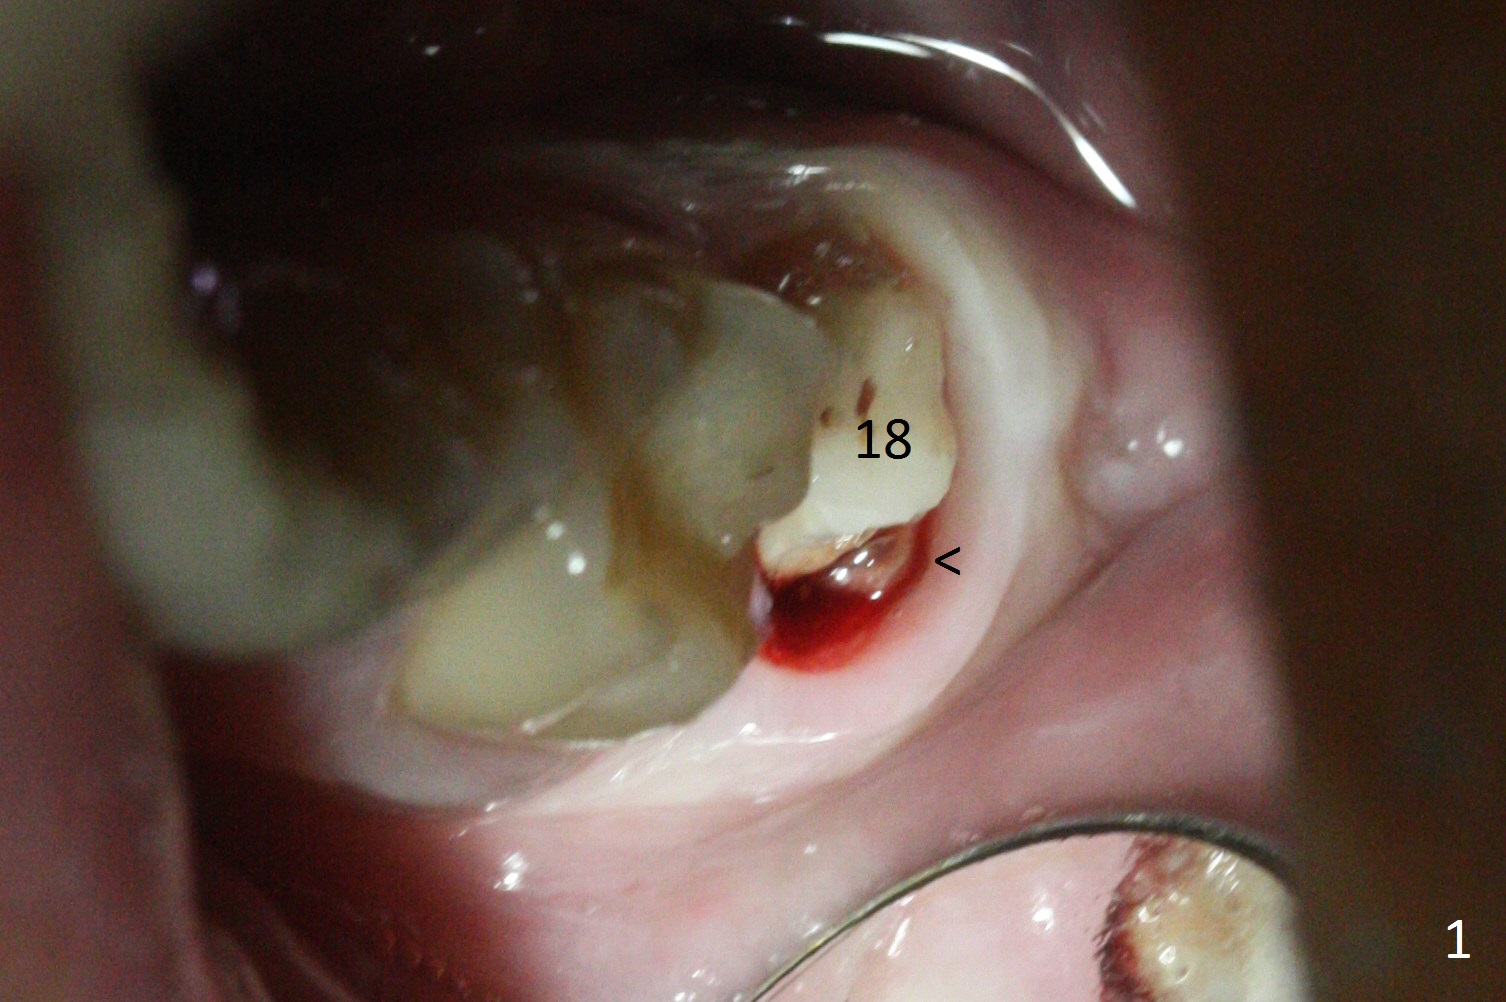

The crown at #18 dislodges; there is buccal subgingival caries (Fig.1 <).  The gingiva is blanched after intraligamental injection.  In fact intraop hemorrhage is substantially reduced.